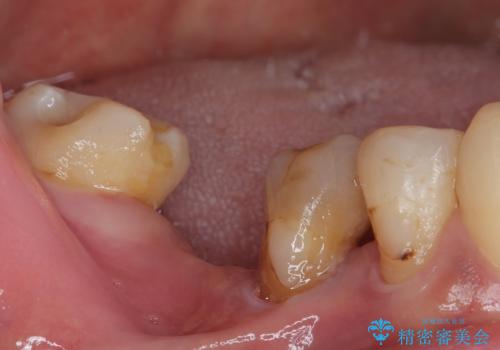

- 奥歯を抜歯してから放置しているとのことで来院された患者様です。

地元の歯科医院では、インプラント補綴治療かブリッジによる治療の二択を提示され、悩んでいらっしゃる状態でした。

歯が割れて抜歯になってしまったとのことと、ブリッジの土台となる手前の歯は既に神経が取り除かれていて、こちらも破折するリスクが高いことから、咬合力に抵抗できるよう、インプラントによる補綴治療を行うこととしました。

手前の神経を取り除いている歯も、合わせて補綴治療を行うこととしました。